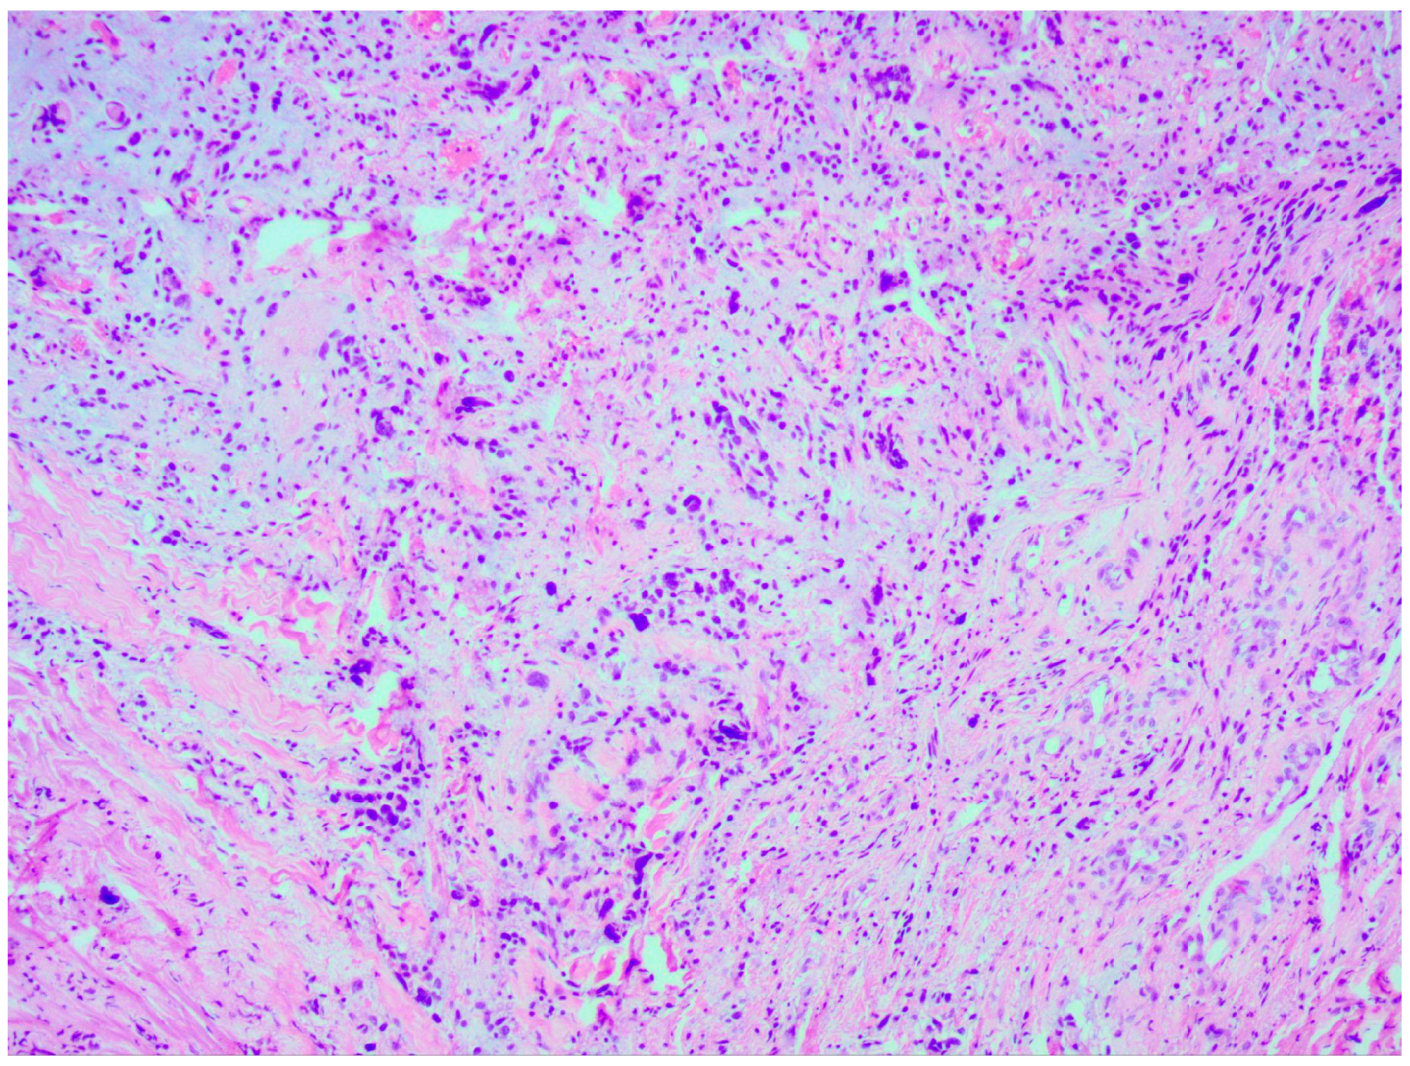

Thorough histopathological analyses highlighted the moderate formation of cellular material, consisting of spherical cells with pronounced nuclear polymorphism, multinucleated tumor cells, and an area of vascular proliferation (Figure 7). Multiple mitotic figures were visualized within the tissue. A histochemical analysis of the tumor tissue revealed the presence of positive glial fibrillary acidic protein (GFAP). Alpha thalassemia intellectual disability syndrome X-linked (ATRX) and isocitrate dehydrogenase 1 (IDH 1 R132H) were both negative. Antigen Kiel 67 protein (KI-67) was positive, but not elevated, around 20–25%.

Histopathological and immunohistochemical examination findings revealed a diagnosis of glioblastoma, IDH-wildtype, WHO Classification Grade 4.

Figure 7. Microscopic image of histopathological analysis, showing spherical cells with pronounced nuclear polymorphism, multinucleated tumor cells, and an area of vascular proliferation.